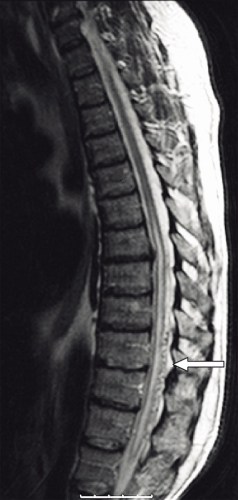

På akutmottagningen tolkades patientens besvär som neuropati, och han behandlades med injektion tiamin (Betabion). Eftersom patienten försämrades ytterligare, genomfördes samma dag akut MRT av hela ryggen, vilken visade ett uttalat ryggmärgsödem från bröstrygg till conus medullaris. Dorsalt om ryggmärgen sågs vidgade blodkärl, varför man misstänkte att det rörde sig om en spinal dural arteriovenös fistel (Figur 1). Neurokirurgisk klinik kontaktades för övertagning.

Diagnostik. Den kliniska bilden och spinal MRT är helt avgörande för diagnosen. Okunnighet hos kliniker eller radiolog kan få som konsekvens att diagnosen ställs för sent eller inte alls, medan patienten utvecklar en obotlig parapares. De typiska fynden vid MRT är ödem och lätt svullnad av ryggmärgen torakolumbalt samt vidgade blodkärl (vener) dorsalt perimedullärt. Ödemet uppvisar hög signal centralt i ryggmärgen på T2-viktade bilder. De vida perimedullära venerna syns i cerebrospinalvätskan som slingriga strukturer med låg signal på T2-viktade bilder och hög signal på T1-viktade bilder efter intravenös kontrastmedelstillförsel.